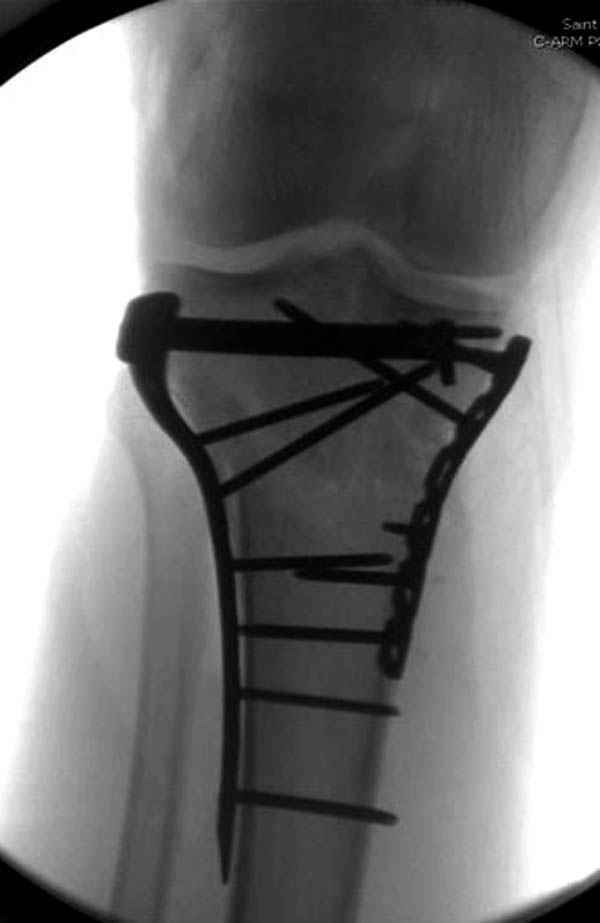

Трудно поверить, что разрекламированная Ортопедическая школа Восточной Украины позволяет такие странные снимки? На прямом снимке сохранен общий контур плато, но не известна судьба импрессии суставной поверхности. На полубоковой?, оставлен без репозиции задне-медиальный отдел, и навряд ли после такой фиксации можно удовлетвориться результатом.

Такая ситуация характерна для многих, когда принимается ошибочное решение, т.е пытаются фиксировать одним имплантом переломы двух мыщелков. Латеральная пластина приемлема только для тех случаев, когда сохраняется интактным медиальный диафизарный кортекс и отсутствует фрагментация на верхушке медиального перелома.

При сложных переломах тибиал плато для своего рода Damage Control мы иногда применяем поэтапную тактику. Сперва оперируется одна сторона, а потом после рекондиции мягких тканей окончательный этап.

Если состояние мягких тканей позволяет, я бы предложил такой метод для вашего больного. Без предварительного планирования будет трудно, но шанс не надо упускать. Всего несколько дней после операции, и такая тактика лучше, чем недовольный молодой пациент.

Доступ к медиальной стороне задний или медиальный, через pes или в пространстве между medial gastroc мышцы.